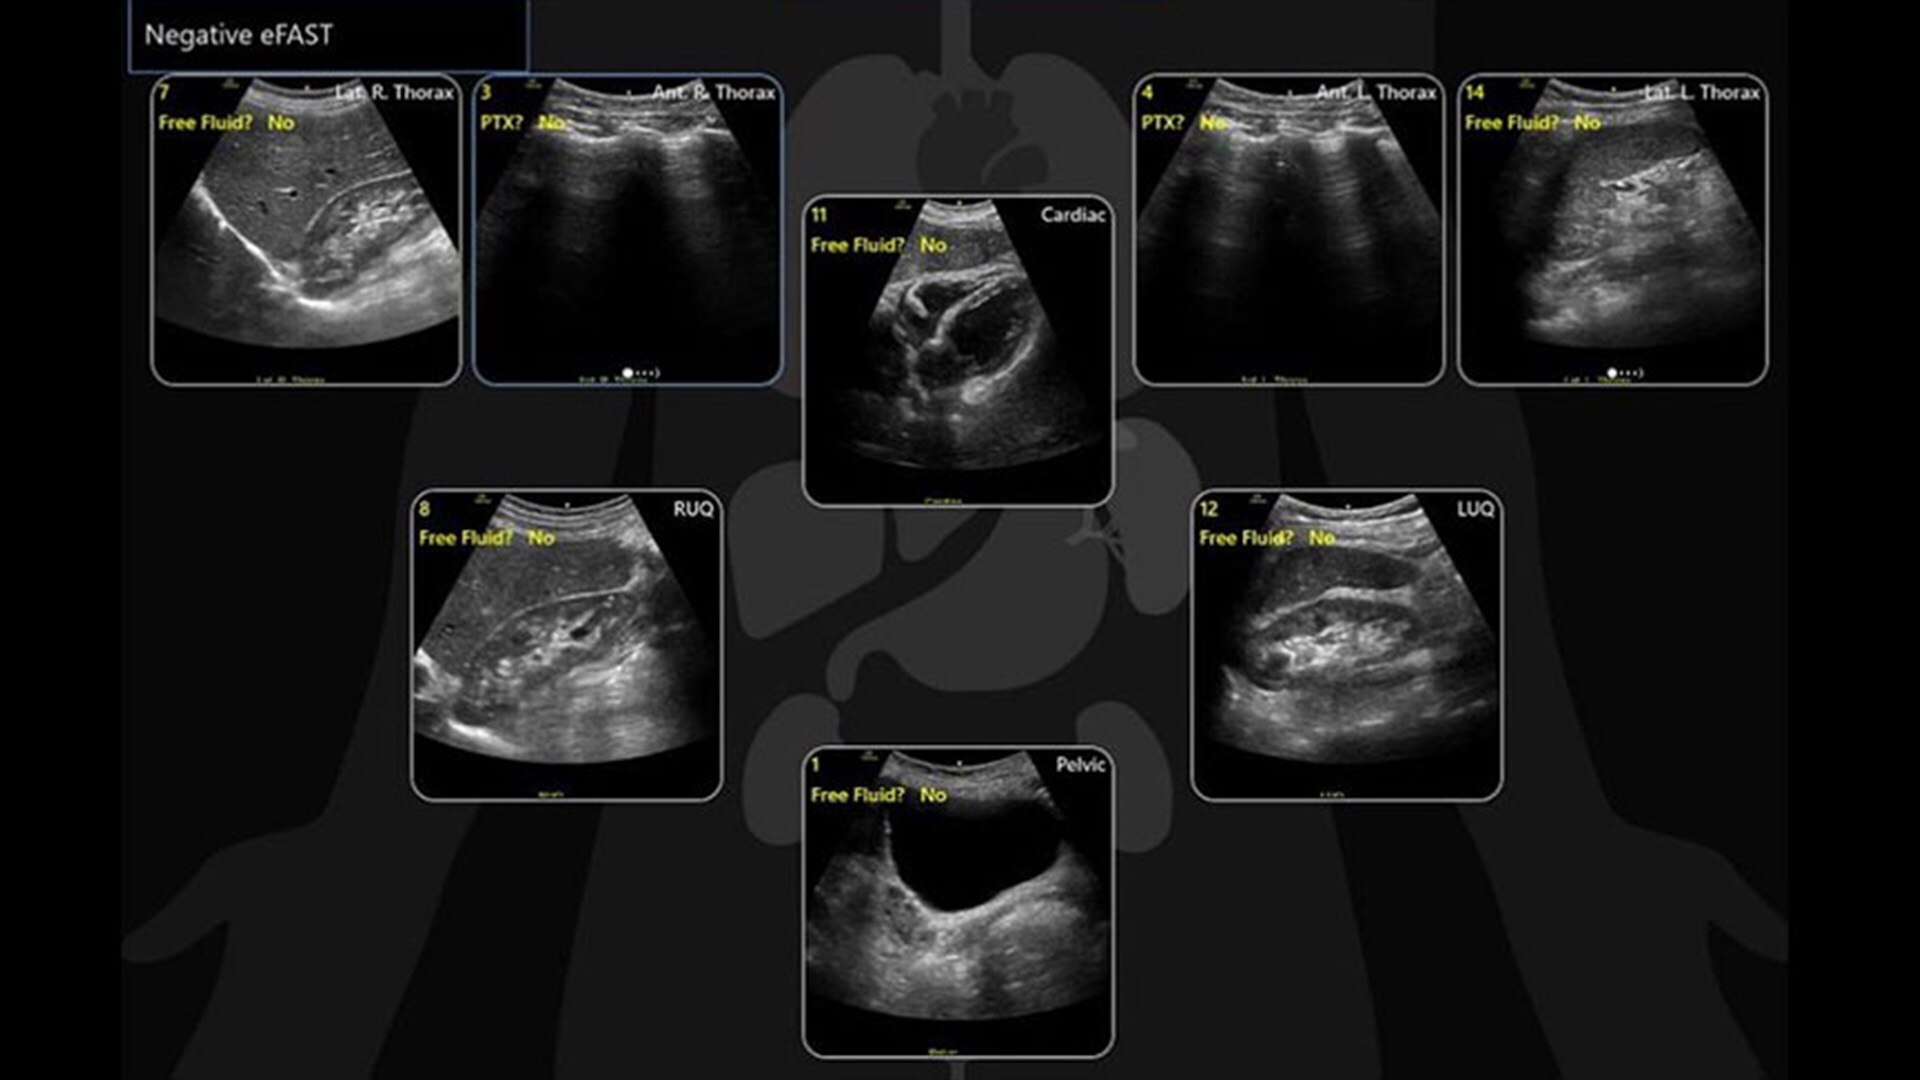

DIAGRAMS

Automated tools streamline workflows

Venue family systems help eliminate busywork at the point of care. Easy documentation and protocol management tools can help reduce keystrokes by up to 80%4 and facilitate exam comparison, and streamline image organization for efficient review. Diagrams specifically streamline image organization for efficient review—allowing you to easily place and auto-label images with a simple tap of the screen.